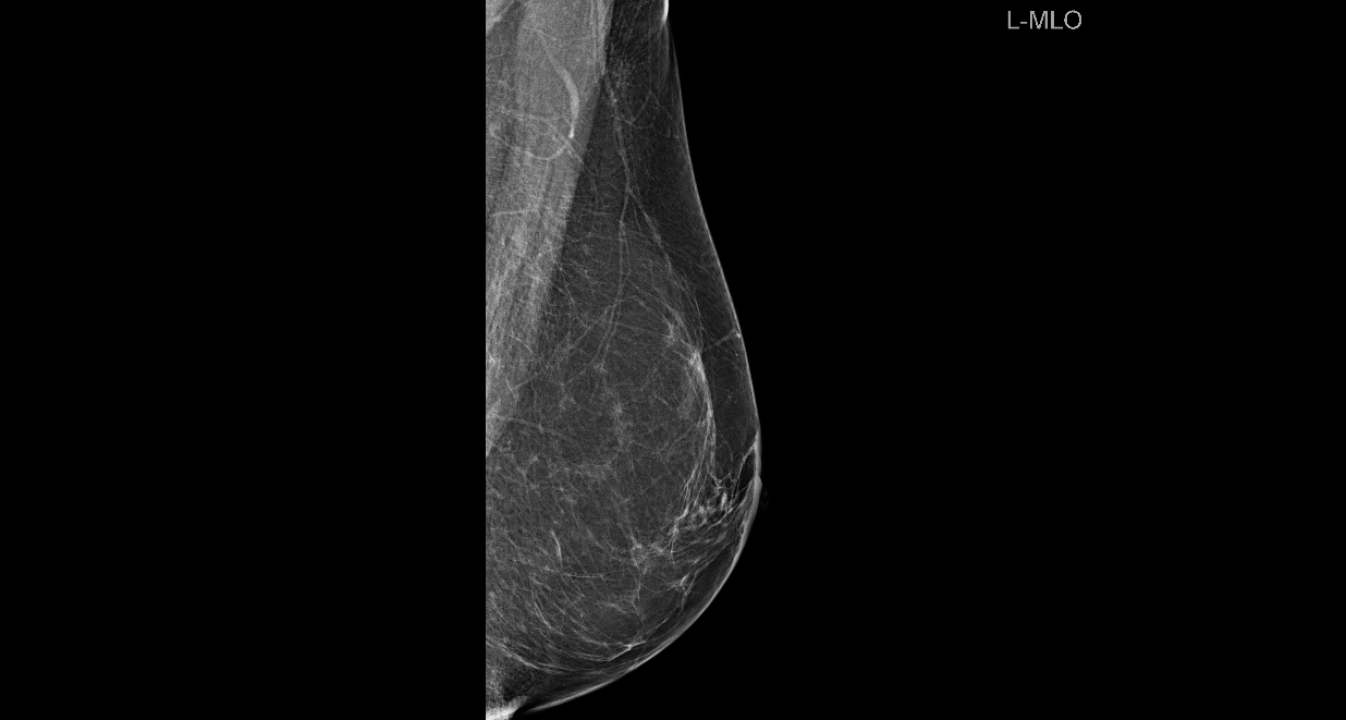

Listopad je mjesec borbe protiv raka dojke, jedne od najčešće dijagnosticiranih zloćudnih bolesti kod žena.